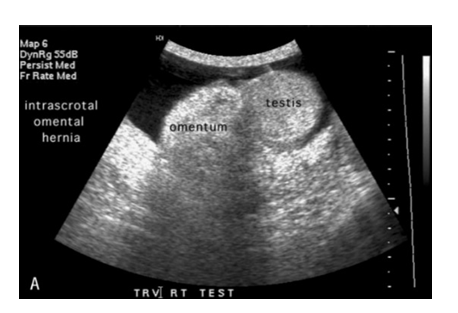

Figure 15 A photograph an intrascrotal hernia.41

Figure 16 A photograph an ultrasound image of intrascrotal hernia.41

Ultrasound technique involves using a liquid gel and hand held transducer probe on the surface of the body. The probe which contains acoustic transducer sends and receives millions of pulses and echoes into the body per second. The sound waves penetrates into the body and hit a boundary between tissues (e.g soft tissue and bone), the waves get reflected back to the transducer probe and then transmitted to the central processing unit (CPU) (Figure 14–16). The CPU is a machine that supplies electric power to the transducer, calculates reflection time of the wave and depth of the tissue interface which cause the wave so as to construct a two dimensional image on the monitor. The procedure usually requires a minimum of 30 minutes.41,42